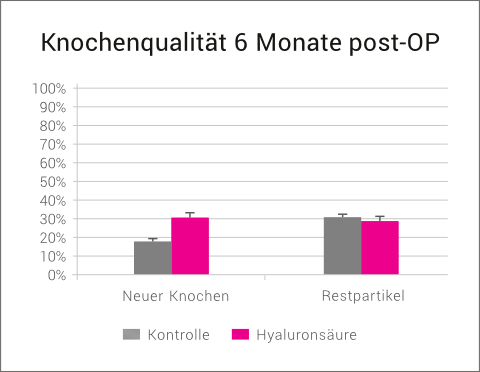

Dies konnte in einer klinischen Vergleichsstudie gezeigt werden. Die Patienten mit ausgeprägten horizontalen Kieferkammdefekten wurden mit einem klassischen GBR-Ansatz (Kombination eines langsam resorbierenden bovinen Knochenersatzmaterial und einer nativen Kollagenmembran) behandelt. In der Testgruppe wurde vor der Augmentation sowohl das Knochenersatzmaterial als auch die Membran mit xHyA vermischt. Nach 6 Monaten konnte in der xHyA-Gruppe ein signifikant höherer Zugewinn an Kieferkammbreite verzeichnet werden (7,7mm vs. 4,4mm).26

Eine histologische Begutachtung der Knochenqualität nach 6 Monaten zeigte in der xHyA-Gruppe eine deutlich verbesserte Knochenqualität im Sinne von mehr neu gebildetem Knochen und weniger avitalen Restpartikeln.

Vergleichbare Ergebnisse wurden in einer weiteren klinischen Vergleichsstudie bei externen Sinuslift-Operationen erhalten.28

Die Hyaluronsäure-Gruppe zeigte nach 6 Monaten eine signifikant bessere Knochenqualität als die Kontrollgruppe im Sinne eines höheren Anteils an neu gebildetem Knochen und weniger avitalen Restpartikeln.

Zudem war der Volumenerhalt des augmentierten Bereichs in der Hyaluronsäure-Gruppe signifikant besser als in der Kontrollgruppe (85,5% vs. 71,4%).